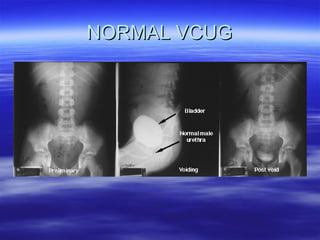

Voiding Cystourethrography (VCUG): Examination Technique and Normal ...

Voiding cystourethrography (VCUG) revealed the normal shape and normal ...

Voiding Cystourethrogram

VOIDING CYSTO URETHROGRAM | PDF

Voiding cystourethrography | PPT